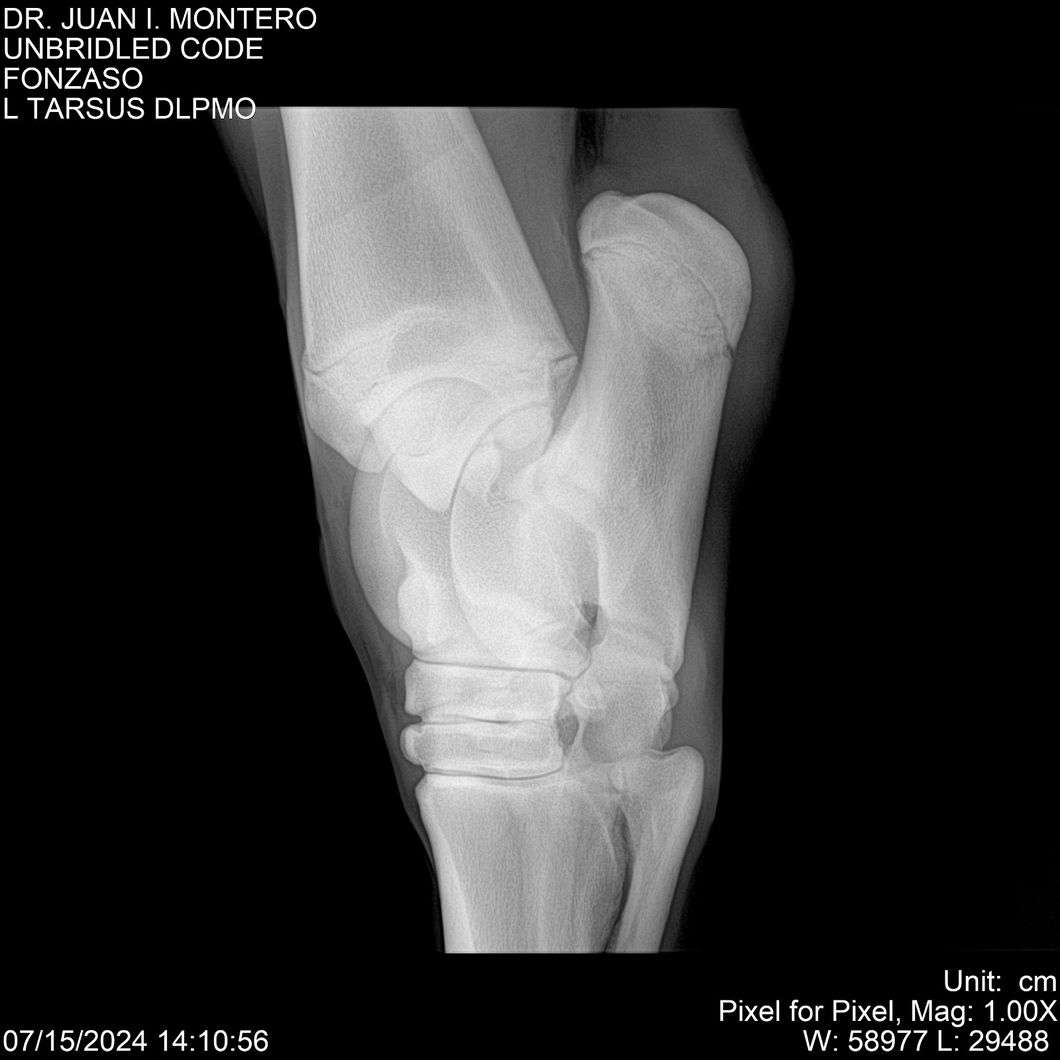

• Empresa: Abelenda N. R., Walter Hugo